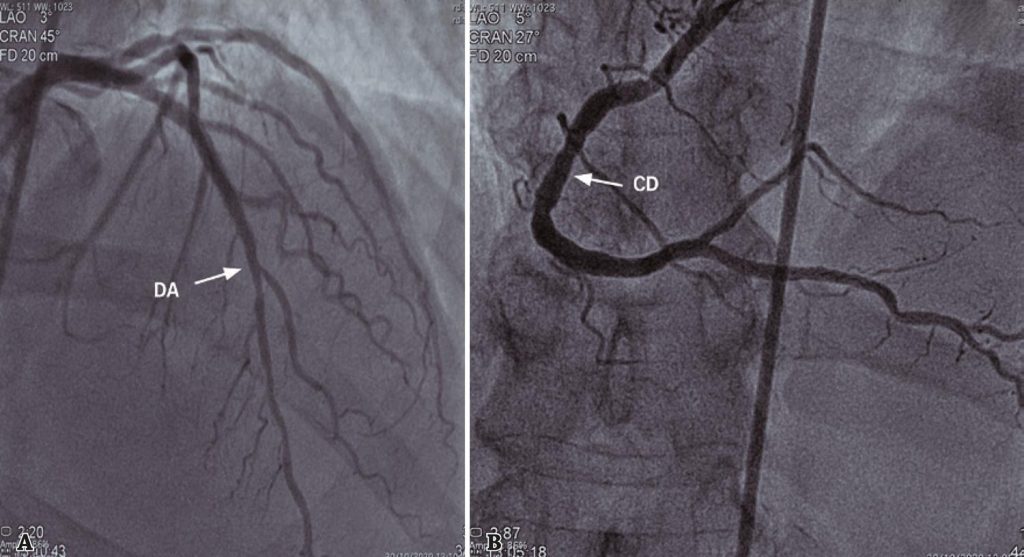

Figura 4

Cateterismo cardíaco de 30 de outubro de 2020. (A) Ausência de lesões significativas na artéria descendente anterior. (B) Ausência de lesões significativas na artéria coronária direita.